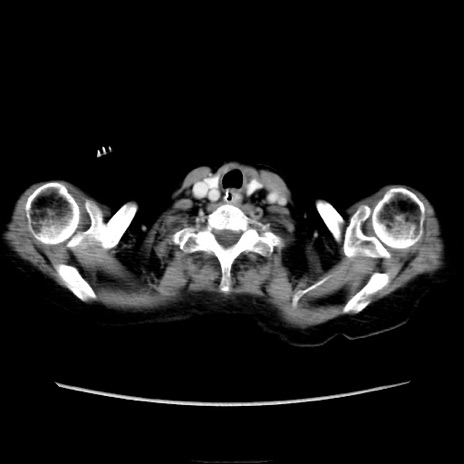

他院CT

横断像